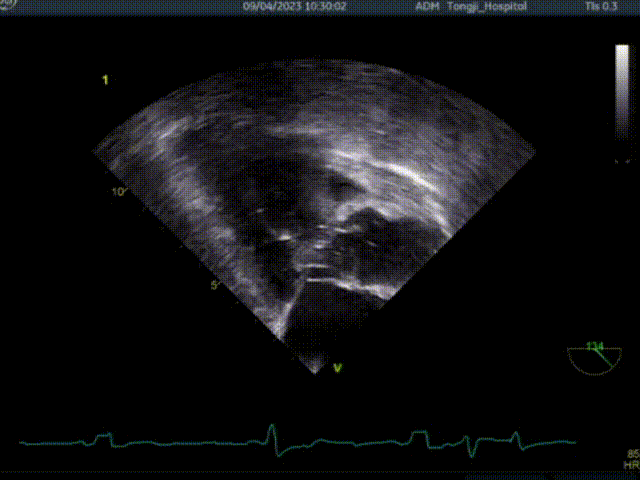

一、经心尖不停跳室间隔切除术

共切除3刀

二、行经心尖介入二尖瓣夹合手术ValveClamp

ValveClamp抓捕瓣叶并收入闭合环内

该患者为老年女性,左室流出道压差134mmHg,二尖瓣前后叶冗长,即便切除了增厚的心肌组织,二尖瓣仍然可能存在反流,同时前叶冗长有阻挡流出道的风险,术前魏翔教授团队就治疗方案进行了充分的商议,最终提出使用两种来自中国原创的新器械(心肌旋切系统+ValveClamp),在同一切口下行不停跳魏氏心肌旋切术加经心尖介入二尖瓣夹合术。